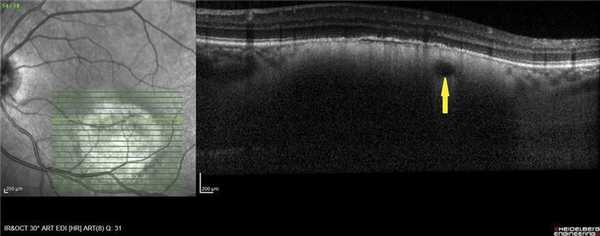

ОНЭ с отеком и дезорганизацией дисков наружных фоторецепторов в макулярной зоне выявлена у 12 больных с ГХ со снижением зрения до 0,02-0,8, проминенцией опухоли 1-4,05 мм и анамнезом заболевания от 1 мес до 15 лет. Наиболее выраженное снижение зрения (до сотых) отмечали в случаях пара- и макулярного расположения ГХ и длительности анамнеза более 10 лет (рис. 5, а), минимальное снижение остроты зрения (до 0,6-0,8) - при длительности анамнеза до 1 года (см. рис. 5, б).

Рис. 5. ОКТ-горизонтальный срез через макулярную зону. а - пациентки Е., Vis OS =0,02, длительность анамнеза 11 лет (ОНЭ, кистозные изменения в макулярной зоне с разрушением фоторецепторов); б - пациентки С., Vis OS =0,7-0,8, длительность анамнеза 6 мес (отечность наружных сегментов фоторецепторов).